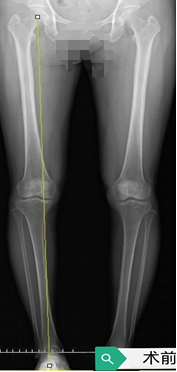

下面是近期一例患者的情况:

患者由术前的O型腿,下肢力线内移,膝内侧负重过度增加;术后恢复正常下肢力线:双下肢直立,并拢。正面观:双膝内侧可以接触,双踝关节可以并拢,膝关节恢复正常负重分布。